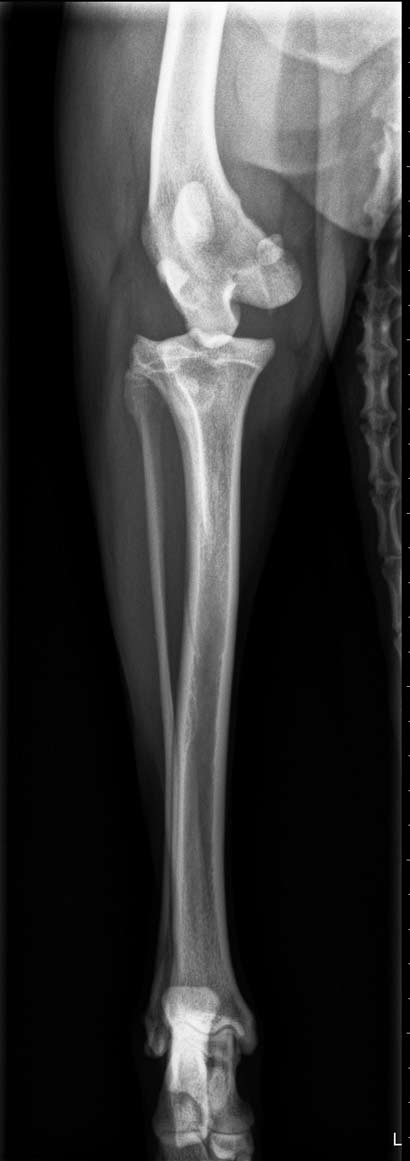

Zuerst wurde planmäßig ein Kunstband in das Knie eingesetzt, sowie eine TPLO vorgenommen. Bei der Hüft-OP konnte dann der Fermurkopf leider nicht in die Pfanne zurückgeführt werden, da er aufgrund der Dauer der Verletzung zu steil verwachsen war (Fehlstellung). Es wurde dann eine Fermurkopfhalsresektion durchgeführt. Danach zeigte Momo noch eine unphysiologische Innenrotation des Kniegelenks. Daher musste dann zur Stabilisierung des Außenbandes ein Faden eingesetzt werden.

In der heutigen Untersuchung wurde festgestellt, dass nicht nur Momo´s Bänder im Knie gerissen sind, sondern dass sie auch noch eine Beckenluxation hat (der Knochen ist aus der Pfanne gesprungen).

Es ist ein extrem trauriger Anblick die junge Hündin so qualvoll gehen zu sehen, wo sie doch eigentlich über Wiesen toben könnte! Wir mussten sofort helfen und haben sie einem Tierarzt vorgestellt. Sie hat sämtliche Bänder im Kniegelenk gerissen. Da ihre Wachstumsfuge ebenfalls in Mittleidenschaft gezogen wurde und der Knochen bereits verformt ist, geht der TA davon aus, dass Momo seit vielen Wochen oder gar Monaten mit ihrer Verletzung leben musste.